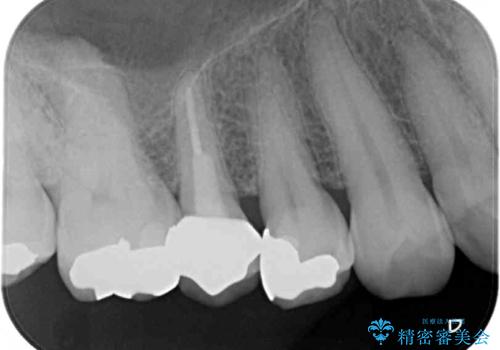

- 歯肉が退縮したためにクラウンの縁や歯根が見えてしまっていることを気にして来院された患者様です。

また、歯肉が黒く変色していることも気になるとのことでした。

仮歯に変える際に歯肉の一部を切除し、金属片による変色を除去した後、オールセラミッククラウンにて補綴することとしました。